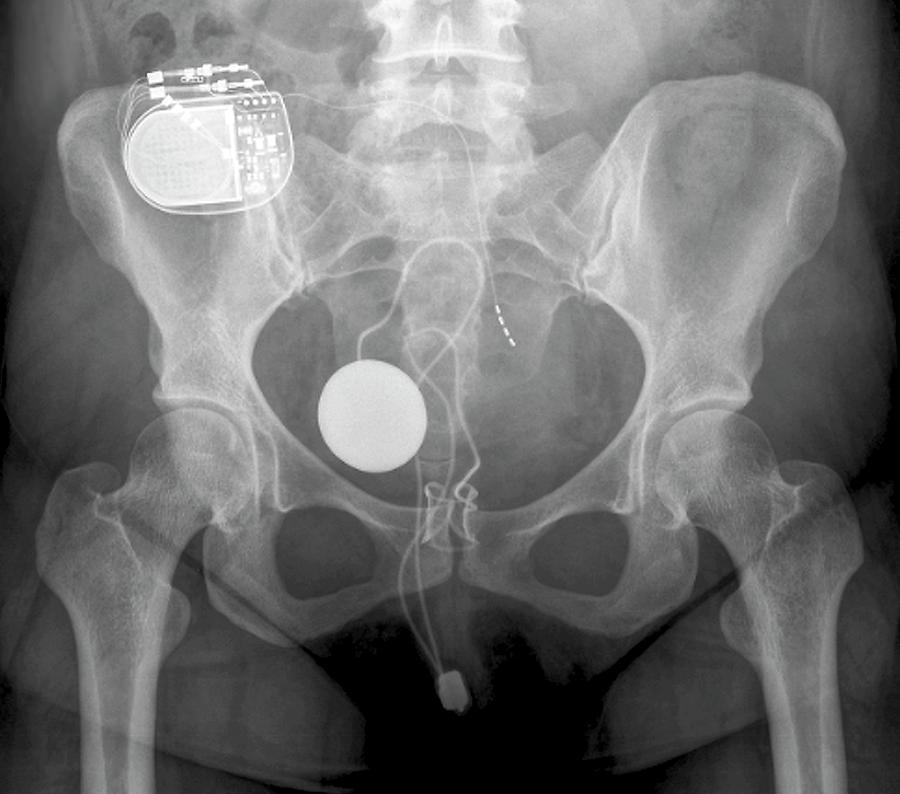

Urinary Incontinence Treatment Photograph by Zephyr/science Photo Library

CT and MR Imaging Features of Artificial Urinary Sphincters, Penile …

Urinary incontinence treatment, X-ray – Stock Image – C009/5516 …